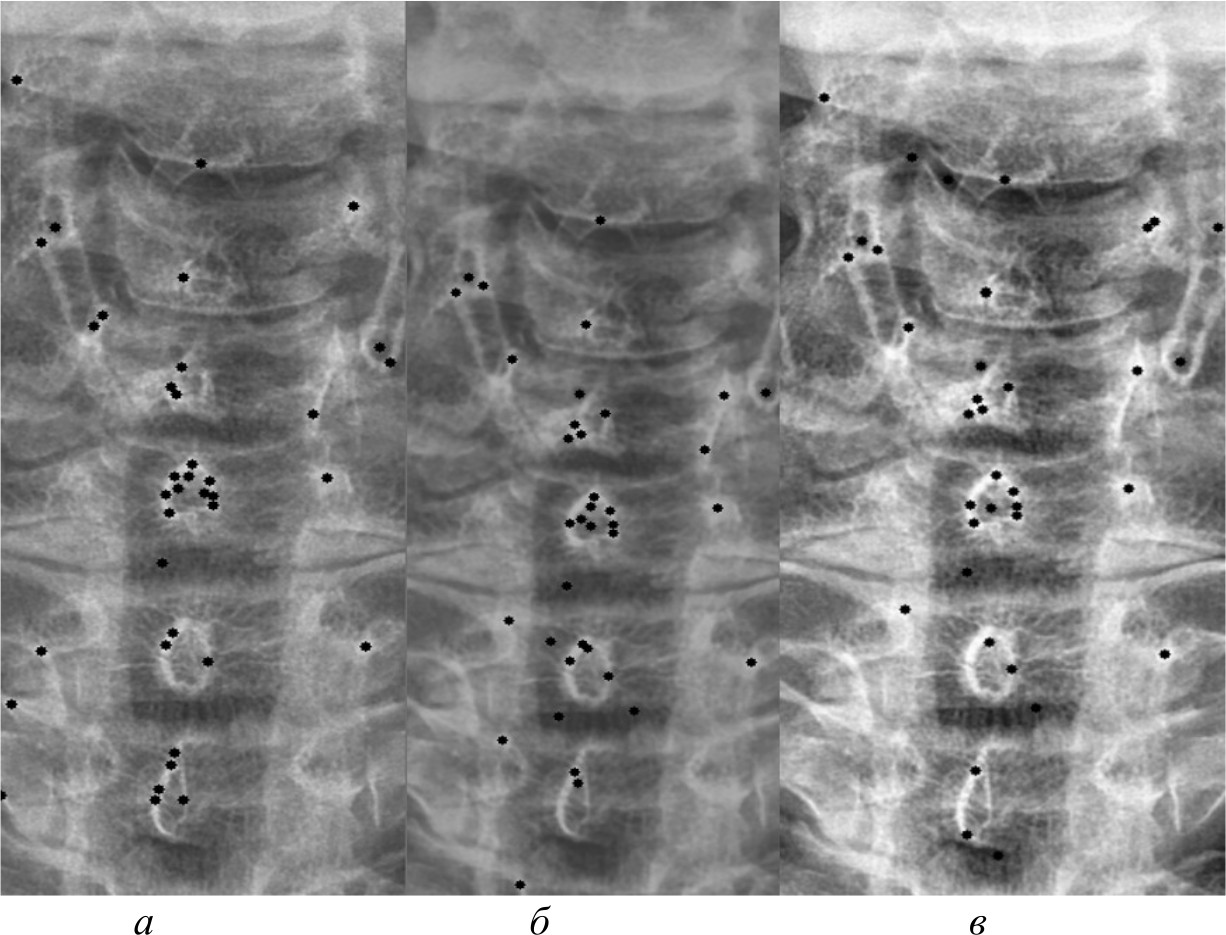

На рис. 4, 5 и 6 представлены результаты работы детектора Харриса, алгоритма Shi-Tomasi и SIFT при различных методах предварительной обработки изображений.

Рис. 5. Результаты работы алгоритма Shi-Tomasi на изображении, полученном при помощи специализированного программного обеспечения (а); результаты работы алгоритма Shi-Tomasi при методе базового отображения в Python (б); результаты работы алгоритма Shi-Tomasi при методе базового отображения Python с применением медианного фильтра (в); результаты работы алгоритма Shi-Tomasi при методе адаптивной эквализации гистограммы (г); результаты работы алгоритма Shi-Tomasi при методе стандартной эквализации гистограммы (д); результаты работы алгоритма Shi-Tomasi при методе гамма-коррекции (е)

Рис. 6. Результаты работы алгоритма SIFT на изображении, полученном при помощи специализированного программного обеспечения (а); результаты работы алгоритма SIFT при методе адаптивной эквализации гистограммы (б); результаты работы алгоритма SIFT при методе стандартной эквализации гистограммы (в)

После получения всех карт анатомических ориентиров составлена таблица и проведен сравнительный анализ. В таблице представлены данные сравнительного анализа методов предварительной обработки и алгоритмов распознавания анатомических ориентиров. В ней представлены следующие данные:

Максимальное количество кластеров, которое может быть выделено, равно 6, так как на рентгеновских снимках выделялась часть спины, включающая 6 позвонков. Некоторые методы выделяют меньше кластеров, в то время как другие – больше; кроме того, часть методов не смогла распознать ключевые анатомические ориентиры вовсе. Это связано с особенностями алгоритмов и качеством предварительной обработки изображений.

На рис. 7 представлена гистограмма, на которой представлено количество ключевых анатомических ориентиров, распознанных при помощи трех алгоритмов на различных предварительно обработанных изображениях.

Рис. 7. Гистограмма сравнительного анализа методов предварительной обработки и алгоритмов распознавания ключевых анатомических ориентиров

Из данных таблицы видно, что наилучшим алгоритмом распознавания анатомических ориентиров является алгоритм Shi-Tomasi. Он распознал максимальное количество анатомических ориентиров вне зависимости от качества изображения, с которым работал, в то время как детектор Harris и алгоритм SIFT не смогли их распознать на изображениях, полученных при помощи базового отображения библиотекой Pillow, а также при применении медианного фильтра. Также алгоритм SIFT не смог найти ориентиры на изображении, полученном при гамма-коррекции.

Проанализировав все методы предварительной обработки и то, как алгоритмы смогли распознать ключевые анатомические ориентиры на них, можно сделать несколько выводов. Наилучшим методом оказалась стандартная эквализация изображений, при которой алгоритм Shi-Tomasi распознавал анатомические ориентиры с точностью около 95 %. Использование специализированного программного обеспечения также показало неплохие результаты, но немного уступало стандартной эквализации по точности распознавания – около 90 %. Остальные методы, такие как применение фильтров или гамма-коррекция, показали более низкую точность, в диапазоне от 35 до 75 %. В свою очередь, применение любого метода предварительной обработки повышало точность распознавания ключевых анатомических ориентиров на 15–25 %. В итоге наиболее предпочтительными методами оказались стандартная эквализация и специализированное программное обеспечение.